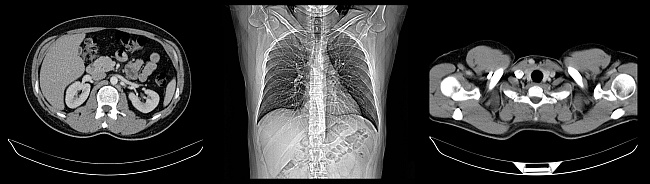

Multislice CT (Computertomographie)

CT

Funktionsweise eines CT-Gerätes

Beim Spiral-Multislice CT rotiert ein Röntgenstrahler bei der Bilderstellung um den Körper des Patienten. Die gesendeten Röntgenstrahlen werden auf der Gegenseite durch ein Detektorsystem empfangen und durch einen speziellen Rechenalgorithmus in ein digitales Schnittbild umgerechnet.

Im Gegensatz zu normalen Röntgenverfahren kann das CT auch eine Volumenstruktur rekonstruieren und so neben Knochen auch Gewebe- und Organstrukturen sehr genau darstellen.